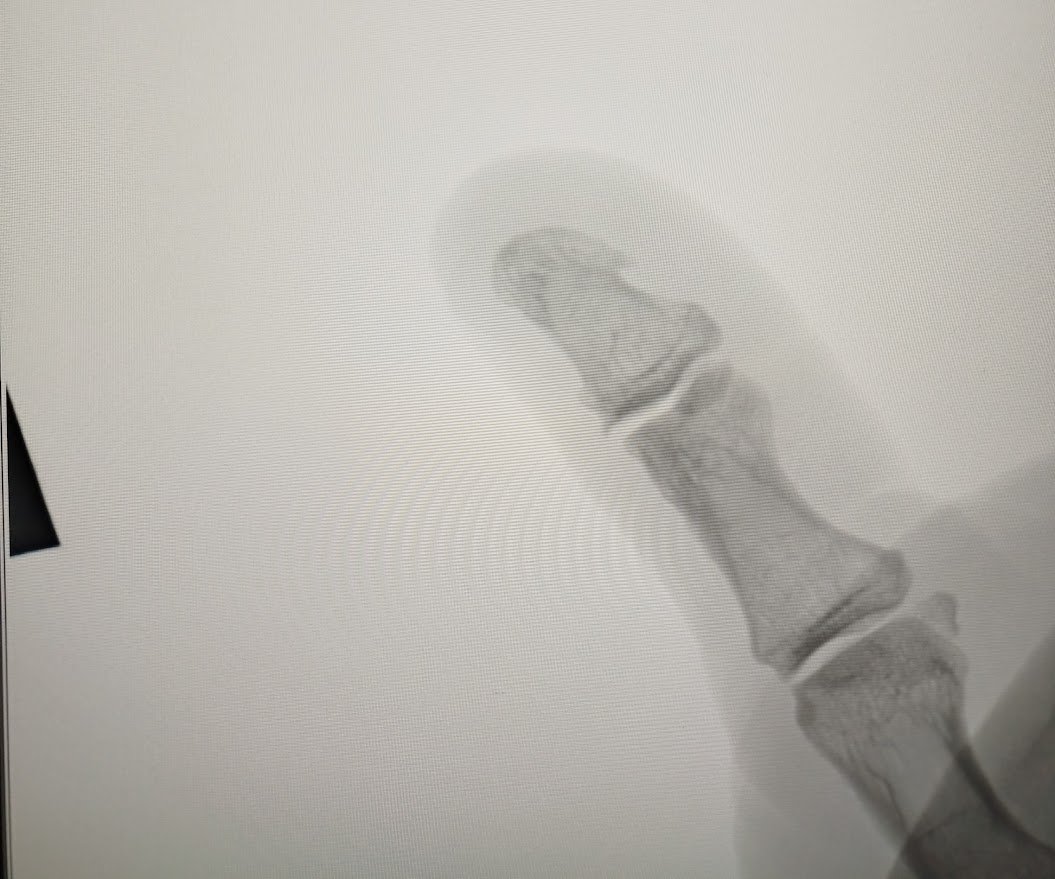

вобщем жила была в пальце у меня какая то штука. ну жила себе и жила, год где то , может быть чуть больше............

14.jpg

потом штука начала слегка беспокоить. т.е не могу я пальцем когда нужно схватить и надавить так как мог раньше. ну типа больновато немного.

сначала 50% могу от того что раньше, потом 30% , потом 10% а потом уже фсе ..... рукой махнуть не могу. пульсирует эта штука ... чужой просится наружу

Вобщем оформились, врач потрогал посмотрел и пошли на рентген, там естественно ничего нет, хотя я до последнего думал что это кусочек медной проволоки .....

13.jpg

12.jpg

11.jpg

просто какая то бусина белая здоровая .... к слову она почти нережется и не колется ... он очень долго ее гонял пытаясь раскрыть ..... раскрыли ... а там ничего .... просто какой то жЫрок , сало .......

и все, преступление раскрыто, когда то год назад. я резко и локально ткнул проткнул палец чем то острым и горячим ... оно сделало пшшш быстро так и я палец отдернул .....

но организьму это не понравилось, он это дело закрыл в капсулу и оно стало рости. когда место кончилось, оно попросилось наружу

к слову сказать палец сейчас визуально меньше чем другой, потому что мясо то сожралось этим чужим ......